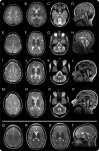

Figure 2. MRI changes with age

MRI of 4 patients with 4H syndrome at 6 (A–D, patient 4H-52, row 1), 12 (E–H, patient 4H-53, row 2), 23 (I–L, patient 4H-58, row 3), and 40 (M–P, patient 4H-94, row 4) years of age. The axial T2-weighted images all show diffusely elevated white matter signal, less hyperintense than CSF, consistent with hypomyelination. The signal of the optic radiations is hypointense, indicating myelination. In the youngest patient, there is a small hypointense dot in the posterior limb of the internal capsule (B). All patients show a relatively hypointense signal of the ventrolateral thalamus. The corpus callosum becomes thinner with age (sagittal T1 images, A, L, P, and sagittal T2 image, H). The sagittal images also demonstrate cerebellar atrophy. White matter signal of the middle cerebellar peduncles and the cerebellar white matter is too high on the T2-weighted images; the dentate nucleus appears hypointense as well as the dorsal tegmentum (C, G, K, O). (Q–T) MRI of patient 4H-45 homozygous for c.1586T>A (POLR3B) at age 16 years. Myelination of the perirolandic cortex and the parieto-occipital white matter is relatively good on these axial T2-weighted images, compared to the frontal white matter (Q, R, S). The splenium and the anterior limb of the internal capsule (R) as well as the optic radiations (S) are well-myelinated. There is a small lesion in the right optic radiation (R). No cerebellar atrophy is seen on the sagittal T1-weighted image (T).